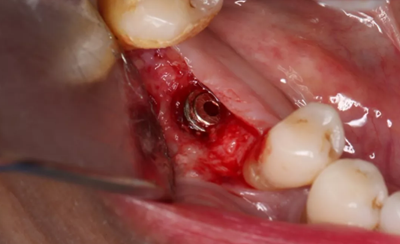

11、常規(guī)植入WEGO種植體一顆

牙槽嵴頂水平切口,翻瓣,牙槽嵴近中較遠(yuǎn)中豐滿(mǎn)。

(攝于2017年4月14日)

12、延期種植手術(shù)過(guò)程

使用直徑3mm的環(huán)形取骨鉆切取長(zhǎng)約9mm的柱狀骨標(biāo)本,用于組織學(xué)和顯微影像檢查

由于取骨致窩洞較大,加之缺牙間隙大,只好選擇植入5mm直徑種植體;種植備洞完成后,頰側(cè)骨壁厚度僅約1mm。

植入國(guó)產(chǎn)威高(WEGO)5.0×11mm種植體,檢查種植體位于理想軸位。